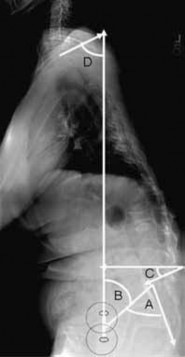

Question 14:

A 14-year-old female gymnast presents with insidious onset of low back pain exacerbated by extension. Radiographs show a unilateral pars interarticularis defect at L5. What is the classic radiographic appearance of this defect on an oblique lumbar radiograph?

Correct Answer: Scottie dog with a collar

Explanation:

Spondylolysis, a defect in the pars interarticularis, classically appears as a 'collar' or 'break' around the neck of the 'Scottie dog' on an oblique radiograph of the lumbar spine.